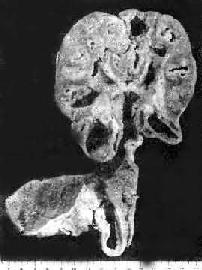

图18-14 结核性脑膜炎 脑基底部脑膜增厚,有散在的结核结节 (四)泌尿生殖系统结核病 1.肾结核病 最常见于20~40岁。男性多于女性。多为单侧性、双侧性肾结核的发病率约为10%。病变开始于肾皮、髓质交界处或乳头体内。初为局灶性结核病变,病变继续扩大发展则发生干酪样坏死,破坏肾乳头而溃破入肾盂,成为结核性空洞。随着病变在肾内扩大蔓延,形成多数结核空洞,最后可使肾仅剩一空壳(图18-15)。由于液化的干酪样坏死物可随尿液下行,常使输尿管及膀胱感染。输尿管粘膜可发生溃疡和结核性肉芽组织形成,使管壁增厚、管腔狭窄,甚至阻塞,结果常引起肾盂积水或积脓。膀胱三角区往往最先受累,形成溃疡,以后可侵及整个膀胱,可引起膀胱壁纤维化,使膀胱容积缩小(膀胱挛缩)。膀胱的溃疡和纤维组织增生如影响到对侧的输尿管口,可使管口狭窄或失去正常的括约肌功能(关闭不全),造成对侧健肾引流不畅,最终可引起肾盂积水。结核菌也可逆行感染对侧肾。

图18-15 肾结核及输尿管结核 肾实质内多数干酪样坏死灶及空洞形成;输尿管壁增厚,粘膜有多数结核结节及浅表溃疡形成 临床上,可因肾实质破坏而出现血尿。液化之干酪样坏死物在排出时可形成脓尿,尿中可查见结核菌。此外尚有尿频、尿急和尿痛。最初,这些症状是由于脓尿刺激膀胱所致,后来则是由于膀胱出现继发性结核之故。 2.生殖系统结核病男性生殖系统的结核病和泌尿系统结核病有密切关系。结核菌经过尿道可感染精囊和前列腺,以后可蔓延到输精管、附睾,睾丸偶尔也可受累。经血源感染引起之生殖系统结核病较少见。大多数病人双侧同时或先后发病。病变器官有结核结节形成和干酪样坏死。男性生殖系统结核的症状主要由附睾结核引起,前列腺和精囊结核多无明显症状。病侧附睾逐渐肿大,轻微疼痛或无痛,可与阴囊壁粘连,溃破后可形成长期不愈的窦道。 女性生殖系统结核多由血道或淋巴道播散而来,也可来源于邻近器官结核病的直接蔓延,以输卵管结核最多见,为女性不孕的原因之一。其次为子宫内膜,卵巢;子宫颈又次之。 (五)骨与关节结核病 骨、关节结核病多由血源播散所致,常见于儿童和青少年,因骨发育旺盛时期骨内血管丰富,感染机会较多。骨结核多侵犯脊椎骨,指骨及长骨骨骺(股骨下端和胫骨上端)等处。在关节结核中以侵犯髋、膝、踝、肘等关节多见。外伤可为发病诱因。 1.骨结核病变常由松质骨内的小结核病灶开始,以后病变的发展可分两型:比较多见者为干酪样坏死型,主要表现为明显的干酪样坏死,破坏骨质而开成死骨。病变常累及骨周围的软组织,引起干酪样坏死和结核性肉芽组织形成。坏死物质液化后可在骨旁形成结核性脓肿,局部并无红、热、痛,故又有冷脓肿之称。穿破皮肤后可形成经久不愈的窦道。另一种为增生型,比较少见。主要形成结核性肉芽组织,病灶内之骨小梁渐被侵蚀、吸收和消失,但无明显的干酪样坏死和死骨形成。以后病灶可为结缔组织包裹而静止。 脊椎结核是骨结核中最常见者。多侵犯第10胸椎至第2腰椎,少数见于颈椎。病变起于椎体,常发生干酪样坏死,病变发展可破坏椎间盘和邻近椎体。由于病变椎体不能负重,发生塌陷而呈楔形,造成脊柱后凸畸形(驼背)(图18-16)。若病变穿破骨皮质,可侵犯周围软组织,干酪样坏死物液化后可在局部形成结核性脓肿,或沿筋膜间隙向下流注,在远隔部位形成“脓肿”。由于脊椎后凸和椎旁结核性肉芽组织或“脓肿”压迫脊髓,可引起截瘫。